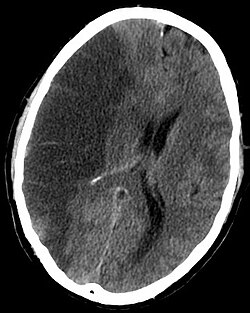

Moždani udar se dijagnosticira putem nekoliko tehnika: neurološki pregled (poput NIHSS skale), CT (najčešće bez kontrastnog pojačanja) ili MR, Doppler ultrazvuk i arteriografija. Sama dijagnoza moždanog udara je klinička, uz pomoć slikovnih tehnika. Slikovne tehnike također pomažu u određivanju podtipova i uzroka moždanog udara. Ne postoji još ubojičajeni krvni test za dijagnozu moždanog udara kkao takvog, iako krvne pretrage mogu pmoći u pronalaženju uzroka moždanog udara.

Slikovne tehnike

Za dijagnosticiranje ishemijskog moždanog udara u hitnoći:

- CT (bez kontrastnog pojačanja): senzitivnost = 16%; specifičnost = 96%

- MRI: senzitivnost = 83%; specifičnost = 98%

Za dijagnosticiranje hemoragijskog moždanog udara u hitnoći:

- CT (bez kontrastnog pojačanja); senzitivnost = 89%; specifičnost = 100%

- MRI: senzitivnost = 81%; specifičnost = 100%

Za otkrivanje kroničnih krvarenja, MRI je mnogo osjetljiviji. Za procjenu stablinosti moždanog udara, pretrege nuklearne medicine SPECT i PET/CT mogu pomoći. SPECT dokumetira moždani protok a PET s FDG izotopom metaboličku aktinost neurona.

U idealnom slučaju, osobe koje su dobile moždani udar smještaju se u „jedinice za moždani udar“, odjel ili namjenski prostor u bolnici gdje rade medicinske sestre i terapeuti s iskustvom liječenja moždanog udara. dokazano je da ljudi primljeni u jedinice za moždani udar imaju veće šanse za preživljavanjem od onih primljenih nedgje drugdje u bolnici, čak i ako se za njih brinu doktori bez iskustva liječenja moždanog udara. Kada se postavi sumnja na moždani udar temeljem povijesti bolesti i fizikalnog pregleda, cilj rane procjene je utvrditi uzrok. Liječenje se razlikuje ovisno o temeljnom uzroku moždanog udara, tromboemboliji (ishemijskom) ili hemoragiji (krvarenju). CT glave bez kontrasta može brzo identificirati hemoragijski moždani udar prikazivanjem krvarenja u ili oko mozga. Ako se ne vidi krvarenje, vjerojatna je dijagnoza ishemijskog moždanog udara.